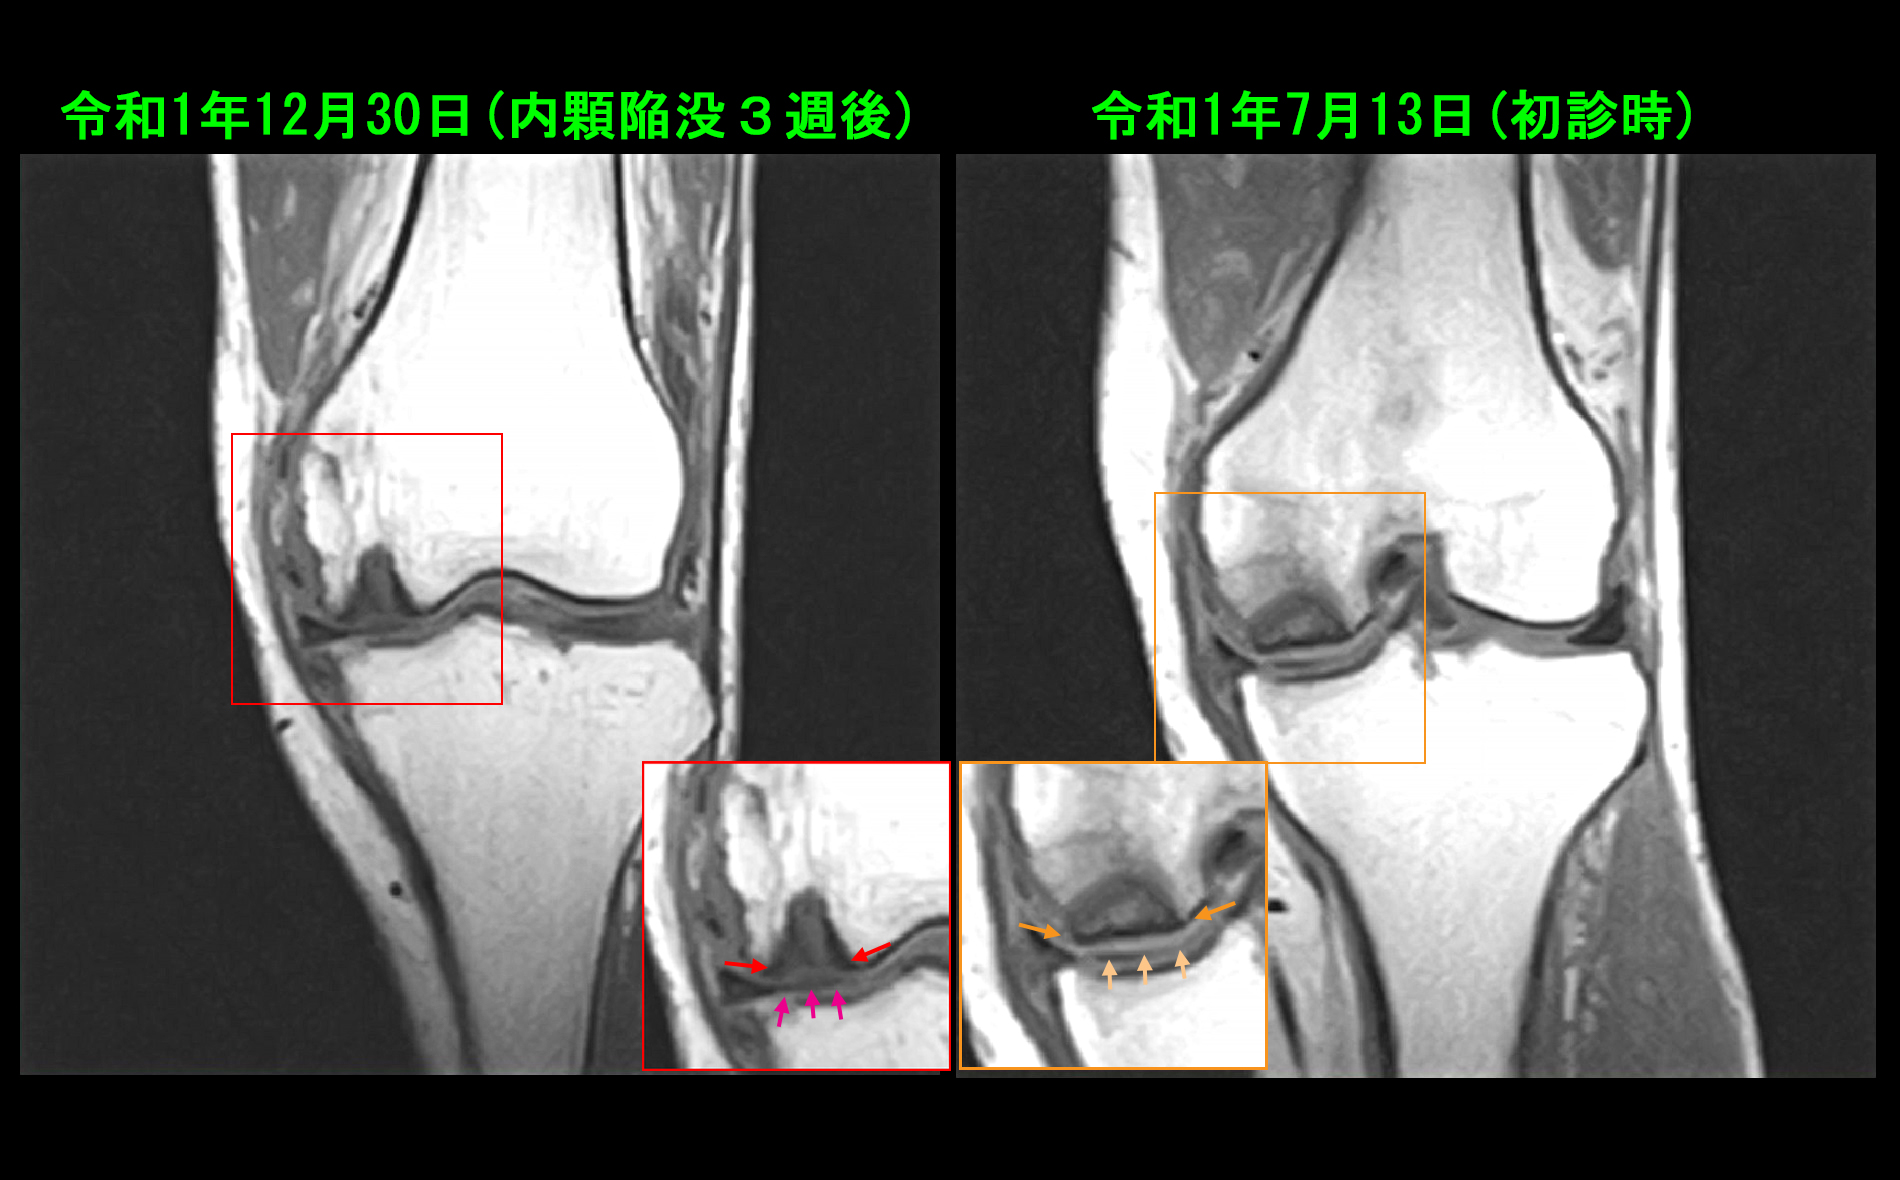

80才 陥凹時MR.jpg

12月30日のMRI検査では骨壊死部の骨皮質(辺縁の黒い線=オレンジ矢印)は消失し、壊死部は深くなっていますが、関節軟骨(薄いグレーの部分)は維持されていると評価可能です(ピンク矢印)。